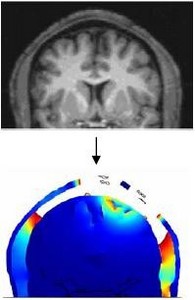

We calculated the spatial distribution of the electric fields induced in the brain during transcranial current stimulation (TCS). The spatial focality obtained using ‘concentric-ring’ configurations is investigated using a realistic MRI derived 3D finite element model of the human head. ... 詳細を見る

Electrical stimulation of the brain involves the application of currents delivered through scalp electrodes to modulate brain activity, known as Transcranial Current Stimulation (TCS). A critical factor for TCS efficacy and safety is the “spatial focality” of induced neuronal modulation. ... 詳細を見る